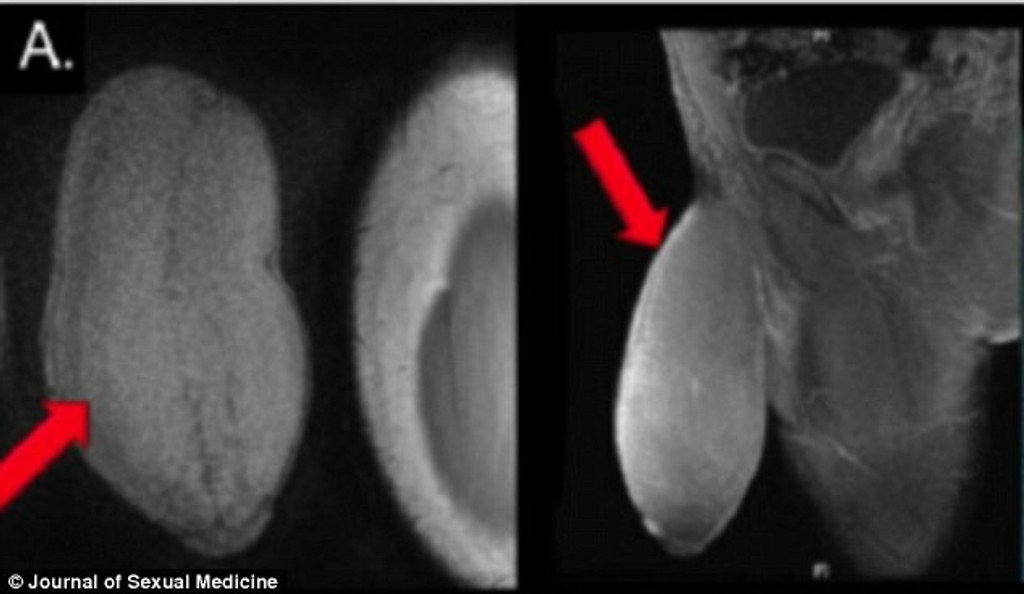

Podľa chirurgov ide o prvú operáciu zmenšenia penisu na svete. Doktorov o zákrok požiadal zúfalý 17-ročný tínedžer. Američan sa sťažoval, že mu mužstvo narástlo príliš rýchlo.

Chirurgovia boli prekvapení, keď sa Američan sťažoval na to, že jeho penis je veľký a spôsobuje mu to problémy nielen pri pohlavnom styku. Jeho pýcha mala obvod vyše 25 centimetrov. „Pacient trpel častými nechcenými erekciami. Penis mal doslova nafučaný ako balón a jeho tvar bol neprirodzený, " povedal urológ Rafael Carrion z Floridy pre denník DailyMail.

Tínedžerovi pohlavný orgán prekážal aj pri športe. Chirurg sa pred zákrokom radil aj s kolegami, lebo v lekárskych záznamoch nenašiel žiaden podobný prípad. Tínedžer po operácii strávil dva dni v nemocnici. S výkonom chirurgov je veľmi spokojný.

„Nešlo len o kozmetickú úpravu. Operáciou sa výrazne zlepšil aj jeho zdravotný stav," dodal urológ.